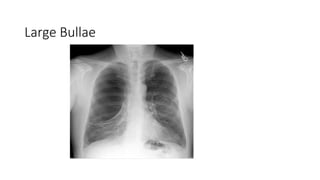

Large Bullae